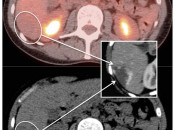

Assessing Lymph Nodes in Lymphoma Cases:

For almost all lymphomas, nodal assessment is performed by comparing the activity of the lymph node with the uptake in the right lobe of the liver. Generally speaking, if the nodal activity is greater than liver uptake, the lymph node represents active lymphoma. This is addressed in detail, here.

Assessing Lymph Nodes in Non-Lymphoma Cases:

Non-lymphoma nodal assessment is more complicated than the technique utilized for lymphoma cases. It involves a combined assessment of “oncologic plausibility”, a node’s relative avidity compared to the liver, and special concern for nodes less than 8.0 mm. This specific algorithm is addressed in detail, here.

Potential Lesions in Solid Organs:

Assessment of a potential malignant lesion within most solid organs involves comparing the metabolic activity of the lesion to the background uptake within that organ (e.g. if a potential liver lesion’s metabolic activity is greater than the background activity of the liver, then the lesion is highly suspicious for malignancy).

There are a few exceptions to this rule, which are addressed in the The Cancers section. For example, many adrenal lesions are assessed by comparing their activity to the liver, not to the adrenal gland itself.